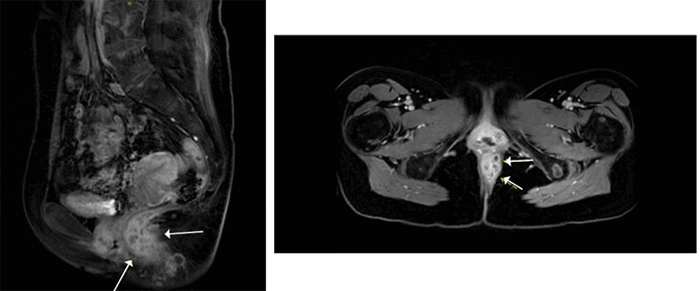

The patient was discharged two days later. and continued to receive systemic chemotherapy with doxorubicin. During her course, an MRI was obtained (Figure 3) to assess the lesion further, showing tumor involvement of the external sphincter and invasion of the ischiorectal space. Two months later, she died peacefully in her sleep.

Figure 3. MRI Performed One Month after Surgery Showing Tumor Involvement of External Sphincter and Invasion of Ischiorectal Space. Published with Permission